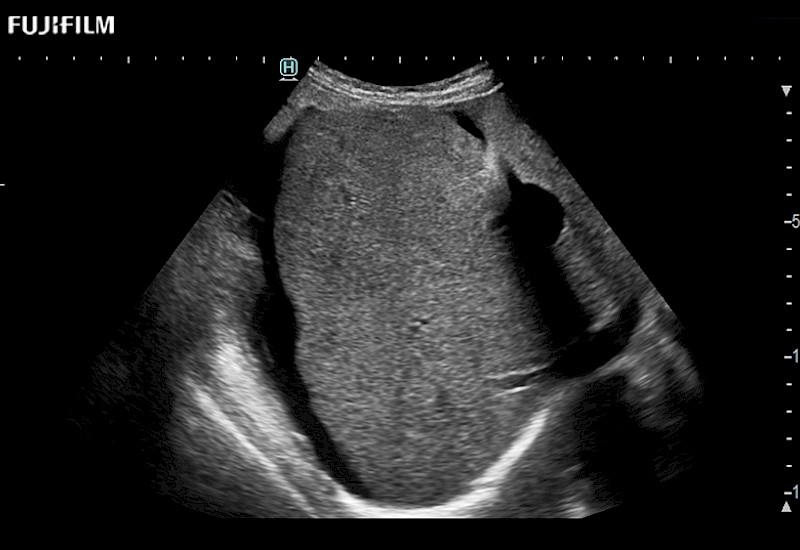

The ARIETTA 750 incorporates all of the proven technologies and functions that medical professionals have come to expect from Fujifilm Healthcare.

ARIETTA 750 is the definitive diagnostic ultrasound solution for any clinical setting - Private Office, Imaging Center, or Hospital. The ARIETTA platform provides the ultimate in clinical performance with its state-of-the-art features and large user-friendly display.

The ARIETTA 650 DI combines trusted Fujifilm Healthcare technologies and features tailored for surgical oncology.

Designed to meet the demands of surgeons, the ARIETTA 650 DI offers precise guidance. Its advanced capabilities and large, intuitive display offer accurate and efficient care in operating rooms and specialized surgical settings.